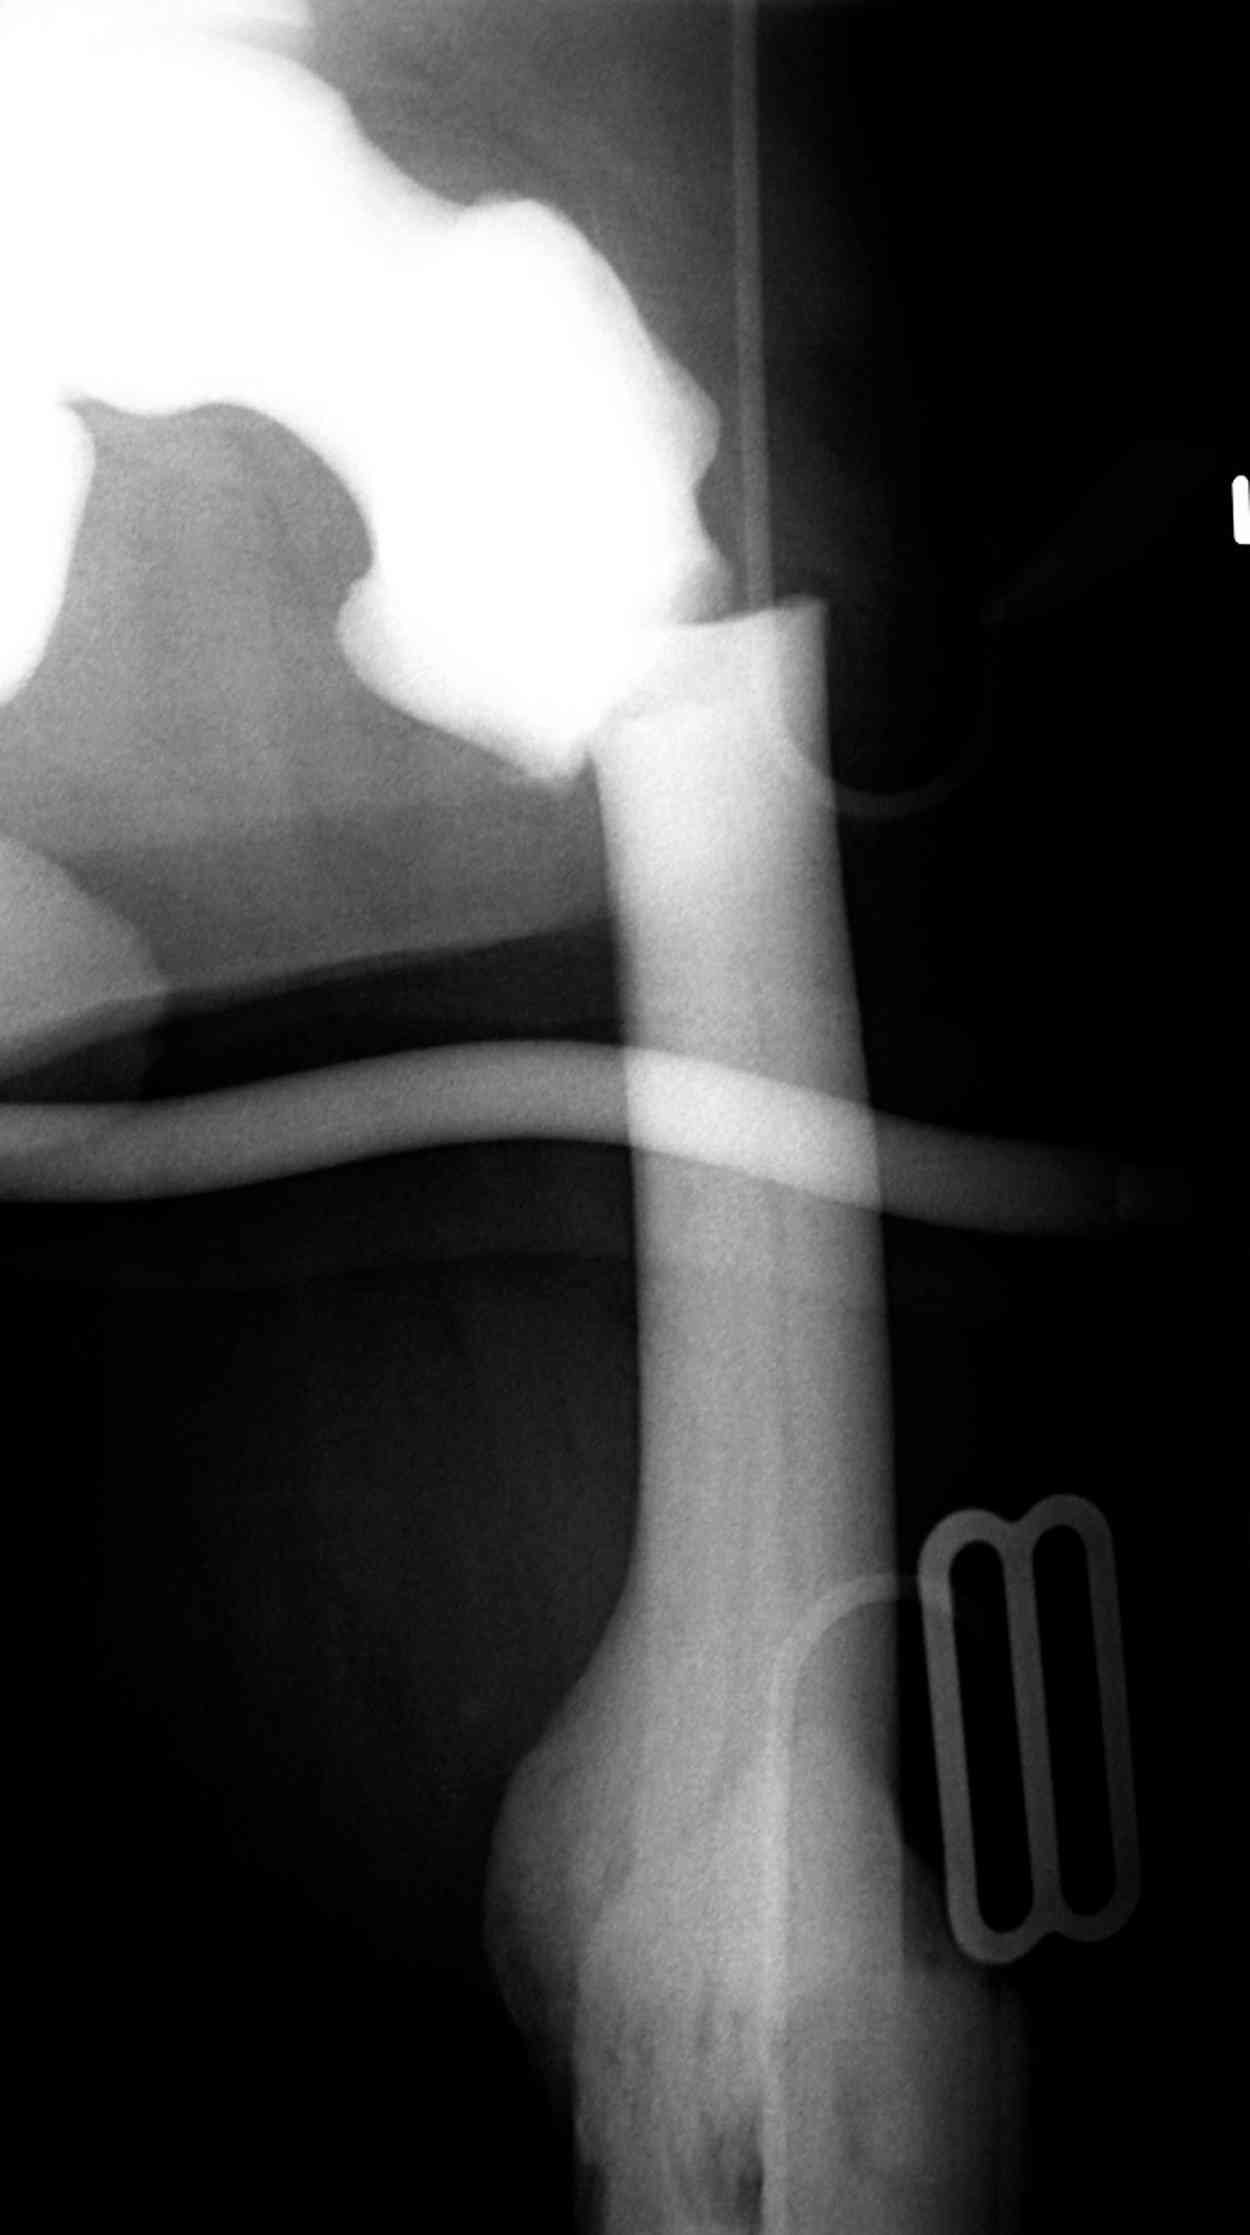

“При лечении переломов у больных с остеопетрозом (в прошлом году был случай) необходимо быть готовым к длительным операциям из-за трудности

обработки традиционными методами "мраморной" кости, иметь в наличие достаточное количество свежих острых инстументов и персонала при необходимости замены (были случаи отстрочки операции на следующий день из-за физической усталости персонала), и надо избежать особо трудоемких операции как интрамедуллярное сверление”.

Не являюсь специалистом по костной патологии, но мне кажется, на ренгенограмме множественные мета-диафизарные образования напоминяющее змееподобных извилистых линии и периостеальные ламинирование очень напоминяет картину остеонекроза (инфаркта) костей, возможно связано с длительным применением стероидов.

При предоставлении дополнительных информации, сканнирования, МРТ и лабараторных данных можно уточнить предварительный диагноз, пока склонен к обширному костному инфаркту, и таких больных рекомендуем лечить сиптоматически.

слайды из прошлегодного случая.